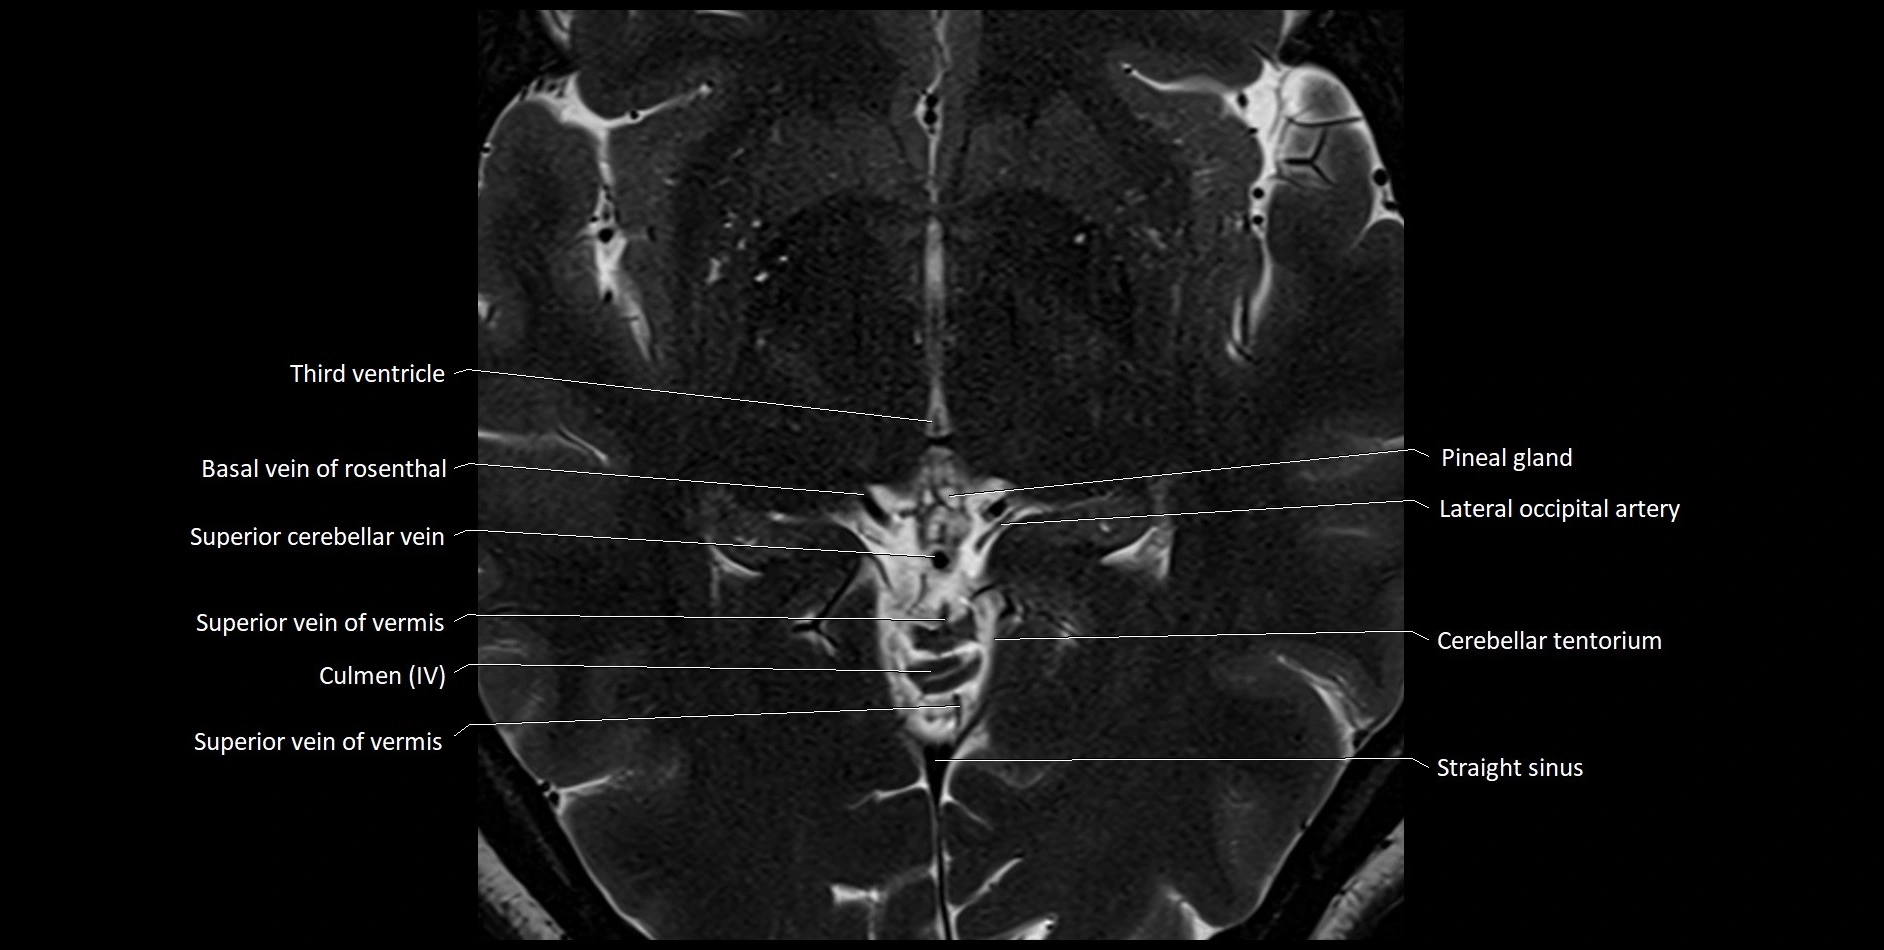

MRI images